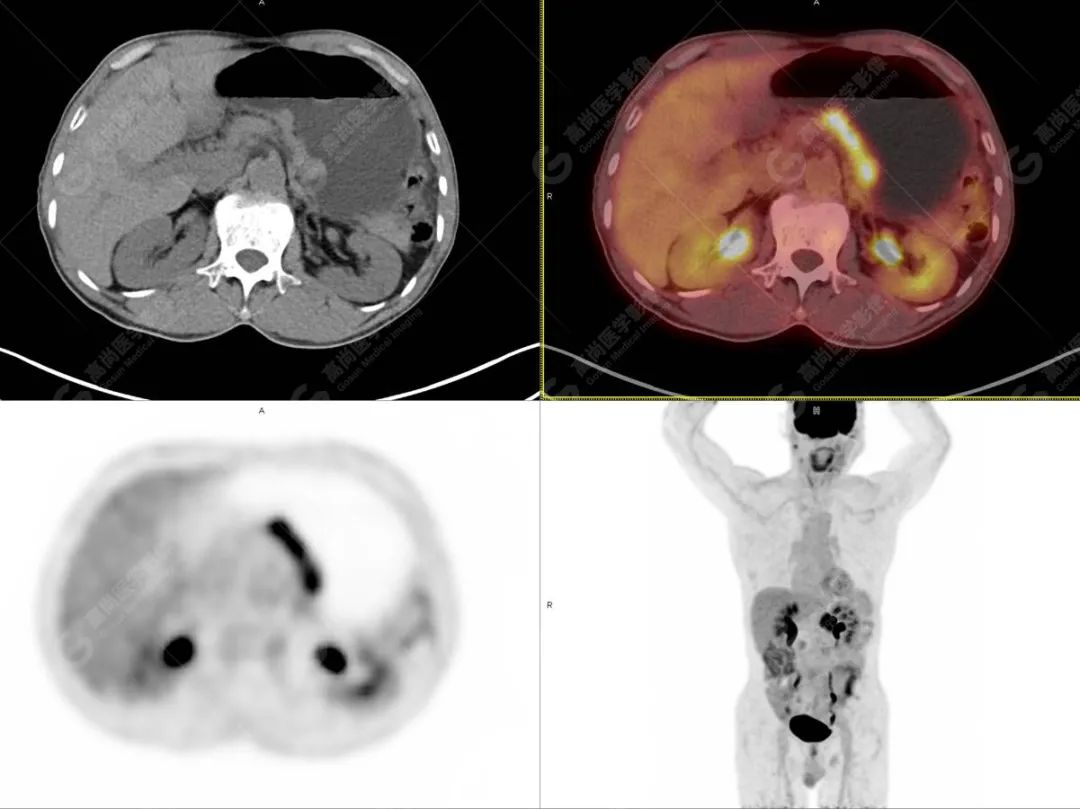

影像诊断:

1. 胃小弯侧胃壁不均匀性增厚,代谢增高,考虑为胃肝样腺癌,建议胃镜活检。

2. 胃周、小网膜囊及腹膜后多发小淋巴结,代谢不高,考虑为转移可能。